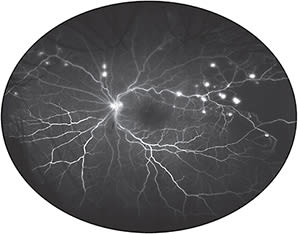

Kiss and colleagues have shown that UWF FA can frequently reveal extensive nonperfusion and neovascularization missed by standard 7-field ETDRS (Figure 1).13 This suggests that conventional imaging can lead to an understaging of DR.14 Because peripheral nonperfusion can now be identified with precision, several investigators have suggested that scatter laser could be targeted specifically to areas of nonperfusion rather than being applied indiscriminately to the entire peripheral retina — thereby potentially limiting damage to “seeing” retina and reducing the side effects of the procedure.15 The efficacy of targeted retinal photocoagulation (TRP), however, still has to be firmly established in prospective trials.16

Figure 1. Optos ultrawidefield fluorescein angiogram of the left eye of a patient with proliferative diabetic retinopathy. Numerous small areas of neovascularization and extensive peripheral non-perfusion, not evident by ophthalmoscopy, are clearly evident by ultrawidefield imaging.

COURTESY SRINIVAS R. SADDA, MD